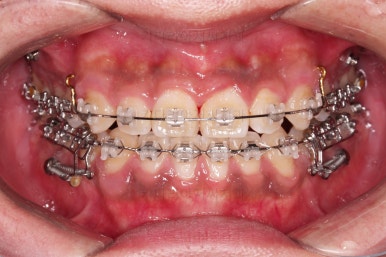

우선 치열이 가지런해졌으면 우리의 목표인 치열을 통째로 뒤로 미는 과정을 진행합니다.

잇몸뼈에 미니스크류라고 하는 아주 작은 임플란트를 식립하고요.

미니스크류를 이용해서 뒤로 당겨주게 됩니다.

어느 정도 아랫니가 뒤로 와서 위아래의 교합이 맞춰졌다 생각들면 윗니도 함께 뒤로 당겨줍니다.

그래야 뻗쳐있던 앞니의 각도도 좋아지고, 코-입술 각도(비순각)도 좋아지기 때문이죠.